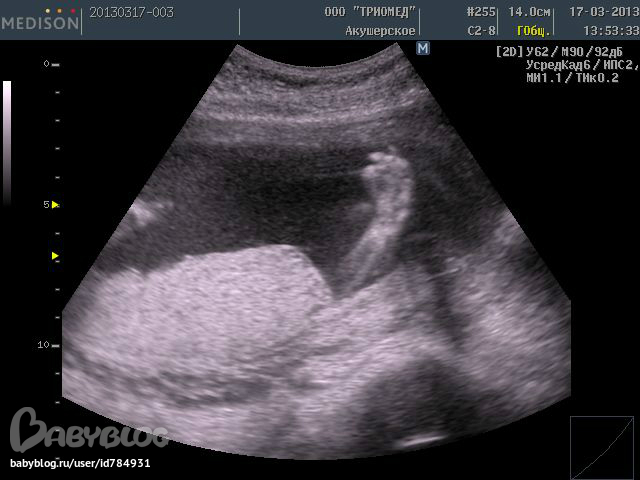

Это зайчик закрывает ручками лицо, не нравится процесс узи:

___________________________